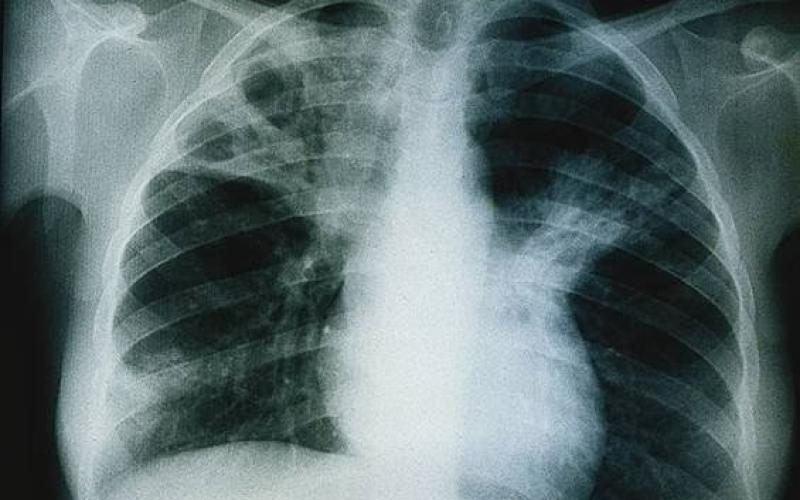

ومن الأعراض التي تظهر على الحالات المصابة بمرض السل الرئوي، السعال المتواصل لمدة تزيد عن اسبوعين، مع ضعف عام بالجسد، والشعور بالقشعريرة، والحرارة وضيق بالتنفس والم بالصدر، إضافة الى فقدان الشهية والوزن والبصاق المصاحب للدم.